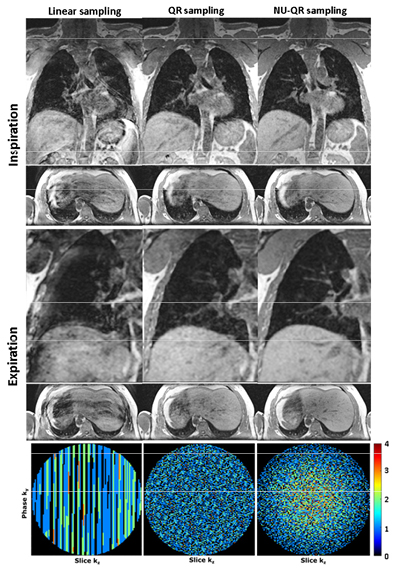

Standard image High-resolution imageThe comparison of different sampling schemes reconstructed for different scan times of 7, 5 and 3 min and Np = Nw = 10 breathing states can be seen in figure 4. Exemplary images of sagittal slices of a volunteer in end-expiratory and end-inspiratory are shown. Moreover, supporting videos V1 and V2 (stacks.iop.org/PMB/63/075002/mmedia) showing an exemplary respiratory motion-resolved coronal slice of data sets for a scan time of 3 min and Nw = 10 gating windows without (Np = 10) and with (Np = 20) consideration of the DC signal derivation. Additionally, figure 5 shows a detailed comparison of a coronal and transversal slice for a scan time of 3 min. Severe undersampling artifacts can be seen in case of linear sampling that strongly affects image quality. In contrast, reduced undersampling artifacts can be seen in case of QR and NU-QR sampling. However, QR sampling shows an increased noise level and incoherent artifacts compared to NU-QR sampling. Accordingly, small vessels in the liver and the lung can be differentiated more clearly in case of NU-QR sampling (see zoomed region). The corresponding distribution of sampled and missing phase encoding steps (kz and ky) after the gating process for the end-expiratory data set are shown in the lower row. Large areas of missing k-space lines can be seen for linear sampling while QR sampling leads to a uniform distribution. NU-QR sampling distributes more points near the k-space center and reduces the sampling density in the outer k-space.

Standard image High-resolution imageFigure 5. Comparison of the proposed method with uniform linear and QR sampling of a volunteer dataset for a scan time of 3 min. Expiratory and inspiratory images are shown in coronary and transversal orientation. Small vessels in the liver and lung can be differentiated more clearly in case of NU-QR sampling (zoomed region). Distribution of accepted and missing k-space lines after gating for the expiratory phase (lower row).

Recently, it was shown that reordering of Cartesian k-space lines using QR numbers considerably improves image quality after respiratory self-gating (Weick et al 2017). The incoherent temporal and spatial ordering allows for a uniform spatial distribution over short periods of time without a priori knowledge about the lines which are accepted for image reconstruction. However, retrospective gating, especially at short acquisition times, may still produce missing lines in the k-space-center and thus coherent artefacts in the reconstructed image. This can easily be overcome by PI techniques as long as the gaps in k-space remain small enough to be correctly reconstructed by the parallel image reconstruction process. In this work a non-uniform QR sampling is presented to address these limitations. The proposed sampling scheme allocates more phase encoding points (ky, kz) near the k-space origin while reducing the sampling density in the outer part of the k-space (see figure 5 lower row). This results in oversampling of the k-space, thereby limiting the risk of missing lines near the center. A related strategy has recently been proposed for respiratory phase-resolved abdominal imaging using self-navigated 4D Cartesian imaging (Küstner et al 2017). However, the current approach uses a 2D QR k-space sampling. The incoherent temporal and spatial ordering of the QR sampling scheme allows for a more uniform spatial distribution after short periods of time compared to pseudo-random sampling. Whereas pseudo-random sampling results in clustering of points, QR schemes provide sampling that is more uniformly distributed and less clustered.

Because most of the energy of an image is concentrated near the k-space center at the low spatial frequencies, only less prominent and more incoherent (noise-like) aliasing artifacts from the low-energy outer k-space at high frequencies are obtained compared to a uniformly sampled k-space.

This can be observed, for example, in the better differentiation of vessels in liver and lung (figure 4). Improved motion artifact reduction can also be observed in radial imaging because the k-space-center is inherently oversampled. Thus, a detailed comparison of the proposed method and radial acquisitions regarding characterization and reduction of motion artifacts would be highly interesting. In a first step, the effect of different motion patterns on the point-spread-function (PSF) and on the noise characteristics (different averaging) have to be simulated for both acquisition strategies. Moreover, phantom and volunteer measurements have to be performed to verify the simulations.